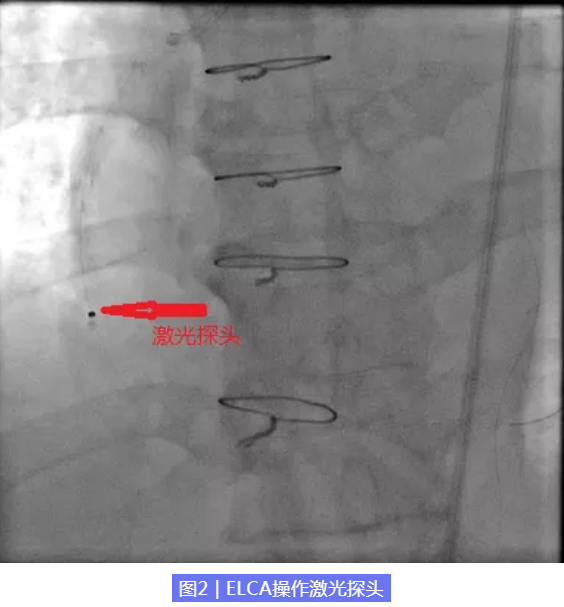

经我院特聘专家北京阜外医院张海涛主任、北京燕化医院心内科李钢主任和王志勇副主任医师全面、综合评估患者病情及血管情况,考虑患者靶病变为桥血管,建议优先解决桥血管病变。经医院心内科介入团队审慎讨论并征得患者同意后,考虑到患者桥血管内存在大量血栓,极易出现无复流现象,决定对患者右冠桥血管行准分子激光销蚀术。一个多小时后,我们成功在患者右冠桥血管狭窄处植入一枚支架,术后患者胸痛症状缓解。

准分子激光冠脉消蚀术采用波长为308nm的激光,作为一种冷激光在人体血液的吸收非常少,而在组织中吸收强。ELCA技术主要通过光化学效应、光热效应和光机械效应三种原理达到治疗效果,即通过发出高能量脉冲引起细胞的碳键断裂,释放的能量使细胞内水温升高致组织汽化产生压力,通过迅速膨胀和收缩导致组织的崩解,消蚀斑块物质,达到改善冠脉血流的效果。消蚀产生的副产品是水、气体和微小物质(直径小于10μm,相当于两个白细胞),避免了血管内栓塞的发生,所以ELCA不易引起无复流及围术期心肌梗死等并发症。

ELCA技术通过消蚀病变血管内斑块,适用于复杂性日益增加的冠状动脉介入手术,可以用于处理支架内再狭窄病变,静脉桥血管病变,血栓病变,球囊不能通过的钙化病变,急性心梗血栓病变和冠状动脉慢性完全闭塞病变(CTO)等。